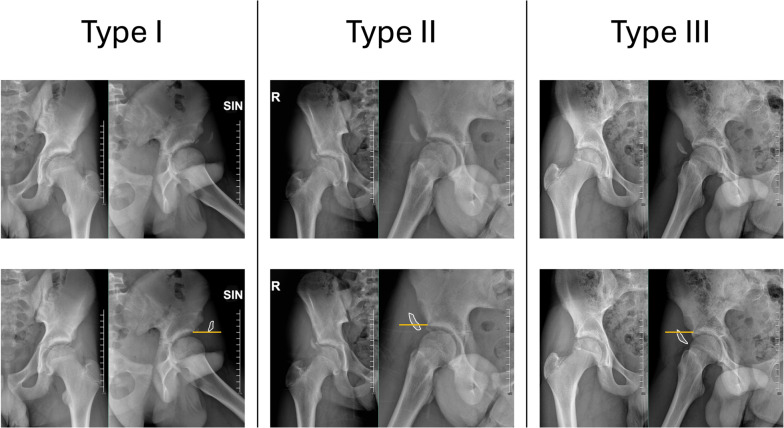

Introduction: Anterior inferior iliac spine (AIIS) avulsion fractures commonly occur in adolescent patients during sports activities. To systematically evaluate fracture severity and guide management, an adaptation of the Hetsroni classification system was used to categorize fractures on the basis of their displacement relative to the acetabular rim. Traditional open reduction and internal fixation reported satisfactory consolidation rates but complications such as lateral femoral cutaneous nerve (LFCN) neuropathies, heterotopic ossifications (HO), and subspine impingement. The objectives of this work are to (1) report short- and mid-term radiographic and clinical outcomes and (2) propose an adapted classification system based on the risk of subsequent subspine impingement.

Results: Eleven male patients with mean age of 14.1 years (range 12.8-15.0 years) were included. Fractures were classified as type I in two patients (18.2%), type II in four patients (36.4%), and type III in five patients (45.4%). The mean surgical duration was 71.4 min (SD 17.1 min), and the average time from injury to surgery was 4.2 days (range 1-11 days). The mean fracture displacement was 18.3 mm (range 15-25 mm). Postoperative scores averaged 89.7 for mHHS (SD 3.1) and 9.7 for UCLA (SD 0.6). Patients were followed for 20.0 months (range 6-47 months, SD 13.3 months). One patient underwent open surgical revision and subsequently experienced temporary LFCN neurapraxia, HO (Brooker 1), and symptoms of subspine impingement.